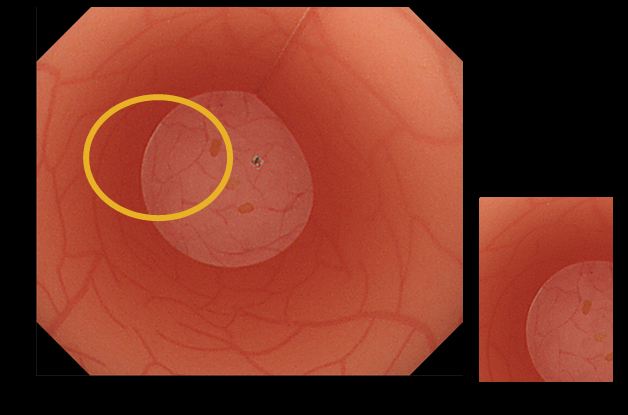

SIF-H190は、高精細CCDを先端部に搭載。より鮮明でディテールの豊かな内視鏡画像により、観察精度の向上に寄与します。

SIF-H190×EVIS X1

SIF-Q260×ELITE